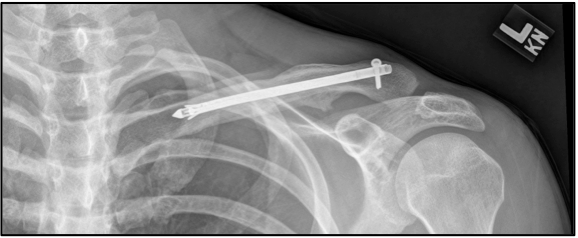

La diagnosi è fatta sulla base di due RX che includono sia l’articolazione acromion-claveare che l’articolazione sterno-clavicolare.

Il fissaggio chirurgico è indicato solo se c’è la presenza di frattura esposta o di un accorciamento maggiore di 1-2 cm. La non-unione dei monconi può svilupparsi anche a causa della formazione di pseudoartrosi fibrosa. In questo caso, infatti, si preferisce la chirurgia attraverso una riduzione open con fissazione interna con placca e bone chips per assicurare il mantenimento della lunghezza della clavicola.

Le recenti evidenze hanno dimostrato che le fratture mediali con un significativo spostamento dei monconi rispondono bene al trattamento chirurgico specialmente negli individui attivi o quelli coinvolti nell’attività overhead. In più, l’operazione chirurgica deve essere sempre consigliata agli atleti d’élite.